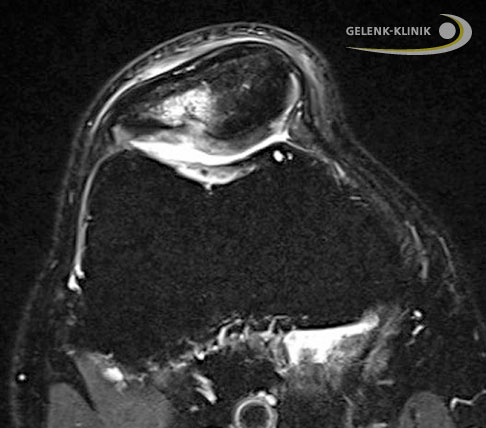

Knorpeldefekt im Kniegelenk mit Knorpelchips Die Aufnahme zeigt einen Knorpeldefekt im Kniegelenk. Der Defekt wurde mit körpereigenen Knorpelchips und Blutplasma des Patienten aufgefüllt. Beides befindet sich unterhalb des Instruments. © Gelenk-Klinik

Minced Cartilage ist ein modernes Verfahren, um Knorpelschäden im Kniegelenk zu reparieren. Gesundes körpereigenes Knorpelgewebe der Betroffenen wird während eines operativen Eingriffs entnommen und mechanisch in kleine «Chips» zerhackt (englisch: to mince, zerhacken). Diese Knorpelchips werden mit körpereigenen Stoffen aus dem Blut des Patienten vermischt und in den Bereich des Knorpelschadens eingebracht. Die gesamte Prozedur findet während einer einzigen Operation statt.